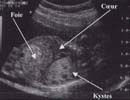

L'échographie met en évidence une masse intra-thoracique [7] :

Le doppler couleur ne retrouve pas de flux à l'intérieur de ces kystes. Il ne retrouve pas non plus de vascularisation aberrante provenant directement de l'aorte.

A ces signes directs peuvent s'associer :